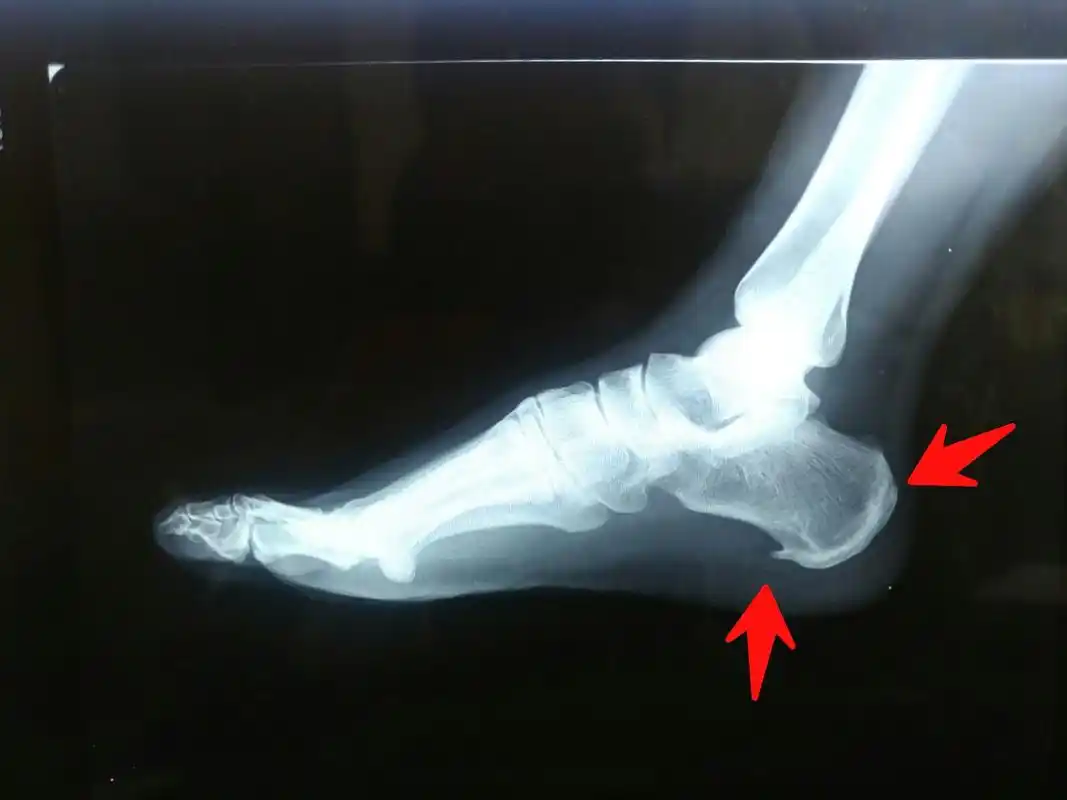

到医院拍片后发现,是足跟着地处长了骨刺.